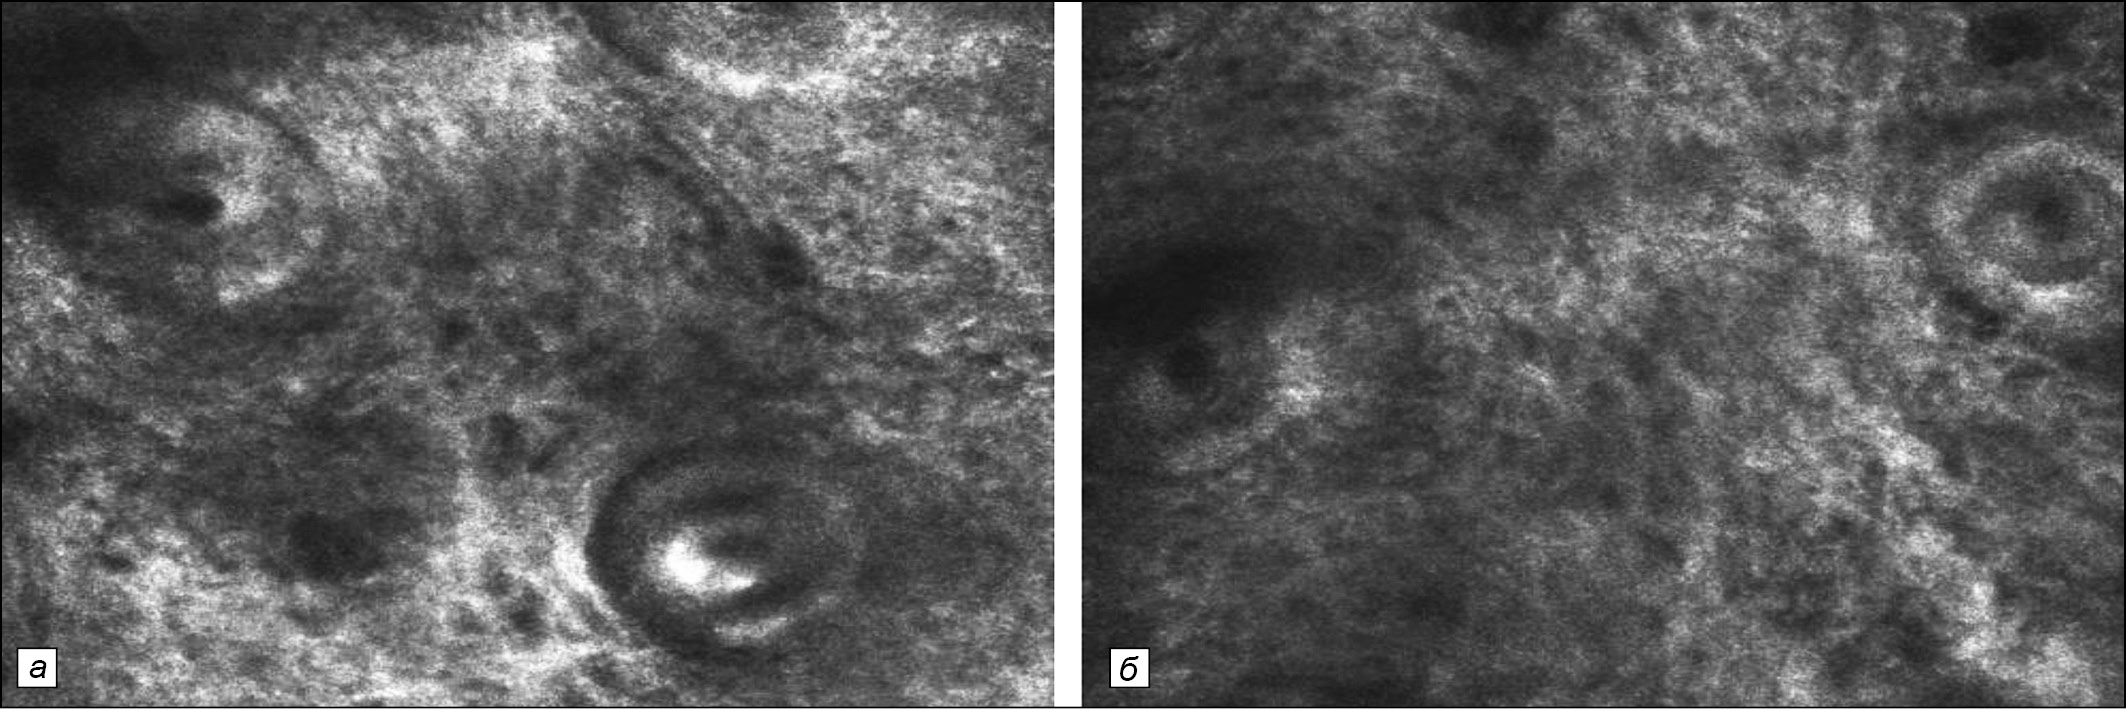

Рис. 5. Та же больная. Конфокальная лазерная сканирующая микроскопия. а – до курса редермализации: определяются значительно расширенные, горизонтально расположенные сосуды, изменения структуры каркаса дермы в виде участков разрежения её структур; б – после курса трансдермальной редермализации: наблюдается выраженное сужение ранее расширенных сосудов, как самых мелких, так и более крупных, в том числе в зоне сосочков дермы. Общая структура верхней дермы приобрела более однородный структурированный вид с нормальным расположением волокон и сосудов.

При проведении КЛСМ, неинвазивном исследовании очагов патологии мы выявили следующие изменения в структурах дермы: значительно расширенные, горизонтально расположенные сосуды, изменения структуры каркаса дермы в виде участков разрежения структур дермы, что свидетельствует об уменьшении количества нормальных волокнистых структур на исследуемых участках (рис. 5, а).

При неинвазивном исследовании дермальных структур методом КЛСМ после курса трансдермальной редермализации мы наблюдали выраженное сужение ранее расширенных сосудов, как самых мелких, так и более крупных, в том числе в зоне сосочков дермы. Общая структура верхней дермы приобрела более однородный структурированный вид с нормальным расположением волокон и сосудов (рис. 5, б).